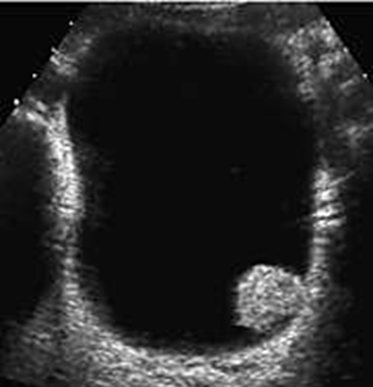

Name this pathology.

What is Bladder Papilloma?